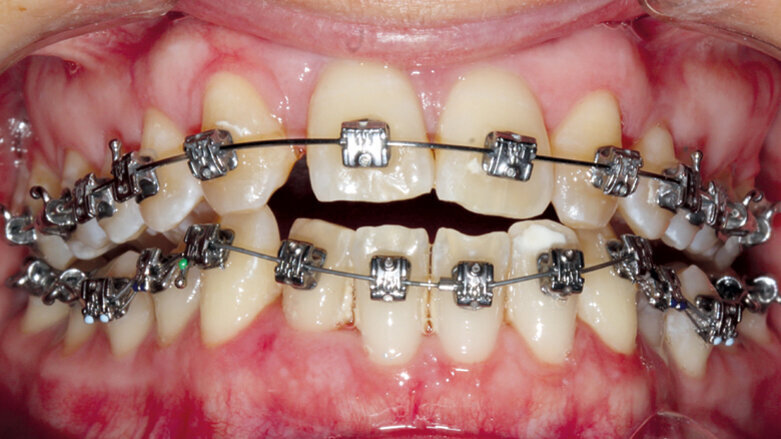

Po nasazení horního i dolního fixního aparátu (Fotografie: Dr. Ana Maria Cantor)

Léčba začala nasazením aparátu Carriere Motion 3D Class III (Henry Schein Orthodontics) pro úpravu sagitálního vztahu čelistí a zároveň aparátu Carriere SLX (Henry Schein Orthodontics) s průměrem slotu 0.022 a preskripcí MBT. Tyto pasivní samoligovací zámky byly nasazeny s obloukem 0.016 Cu Nitanium v horní čelisti pro zajištění adekvátního kotvení. Aparát Motion 3D Class III byl nalepen na špičáky a první moláry v dolní čelisti s intraorálními tahy 6 oz. a průměrem 3/16. Jednalo se o tahy III. třídy, které pacientka nasazovala ke kanylám horních druhých molárů. Nivelizace a harmonizace horního oblouku byla provedena za použití oblouku Cu Nitanium 0.016 a před bukální kanyly prvních molárů byly na obě strany umístěny zarážky tak, aby napomáhaly protruzi horního oblouku.

Díky dobré spolupráci pacientky bylo dosaženo správné interkuspidace během 4 měsíců; negativní schůdek se změnil během pěti měsíců ve skus hrana na hranu (obr. 2a–c). V této fázi byl sejmut aparát Motion a na dolní zuby byl nasazen fixní aparát – Carriere SLX slot 0.022 MBT preskripce, pasivní samoligující zámky (obr. 3a–c).